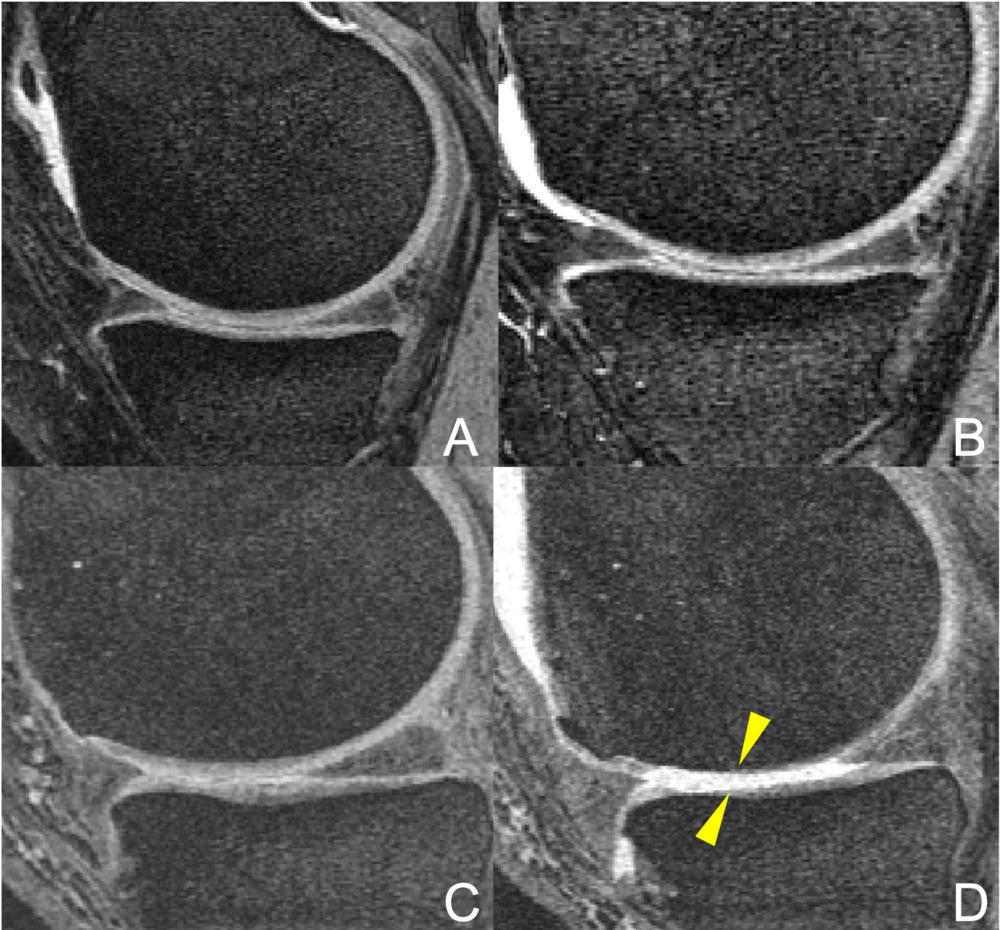

Figure 4. MR images of the right knee at baseline (A, C) and after 48 months (B, D). Obese 76-year-old man in the elliptical trainer group (A-B) and obese 59-year-old woman in the racket sport group (C-D). The woman developed severe cartilage damage at the femur and tibia bones (arrows), with associated damage of the meniscus (asterisk). In contrast, no cartilage damage was seen in the man in the elliptical trainer group (A, B).